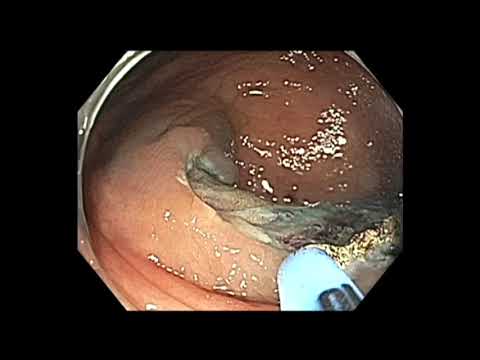

Resekcja zmiany o morfologii LST-G z centralną...

Film przedstawia resekcję zmiany z centralną depresją. Zmiana zwłokniała centralnie. Biosja przed kilkoma tygodniami wykonana przez innego operatora - obecnie stwarza trudność w resekcji "enblock"....